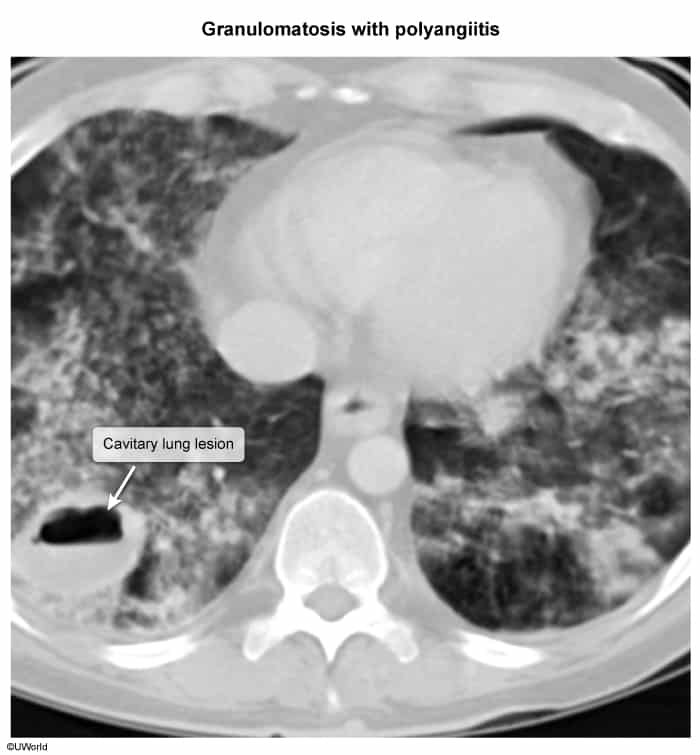

Granulomatosis with polyangiitis (Wegener granulomatosis)

- Obtain a chest X-ray or CT chest

- Supportive findings

- Multiple bilateral cavitating nodular lesions

- Pulmonary hemorrhage